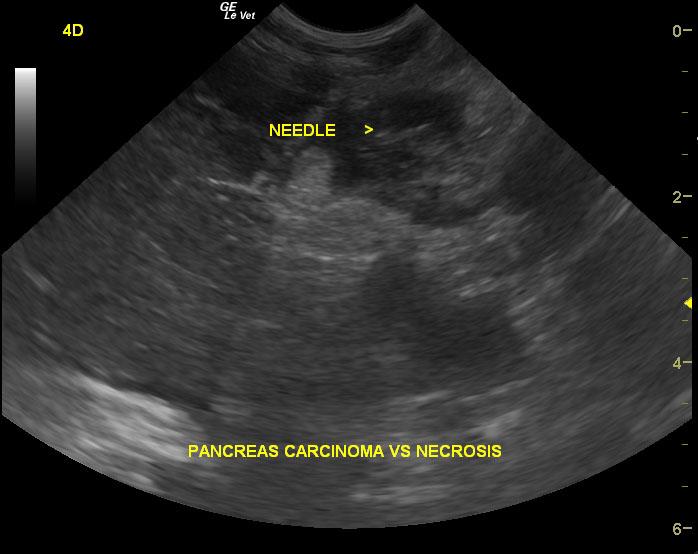

Pancreatic necrosis/abscessation. Potential concurrent pancreatic neoplasia/carcinoma.

Extensive mixed hypoechoic pancreatic parenchyma is noted much of which lacks blood flow on power Doppler assessment. Gastroduodenal thickening is noted with duodenal spasm. Cavitations are noted in the pancreas with echogenic fluid. Extensive hyperechoic fat is noted.

Sampling

FNA revealed necrosis.